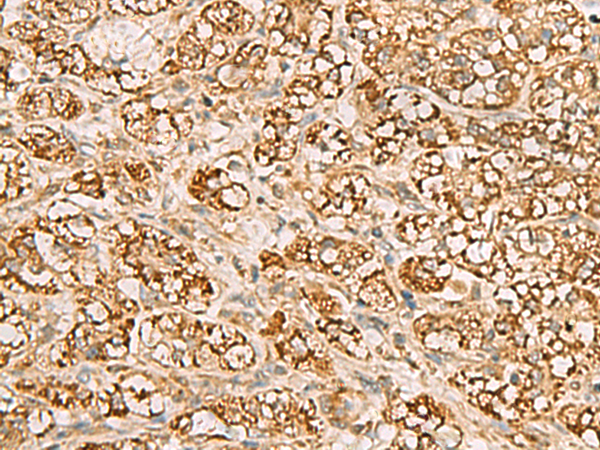

分类: 科研抗体货号: P02868别名: TPMTD应用: IHC反应种属: Human